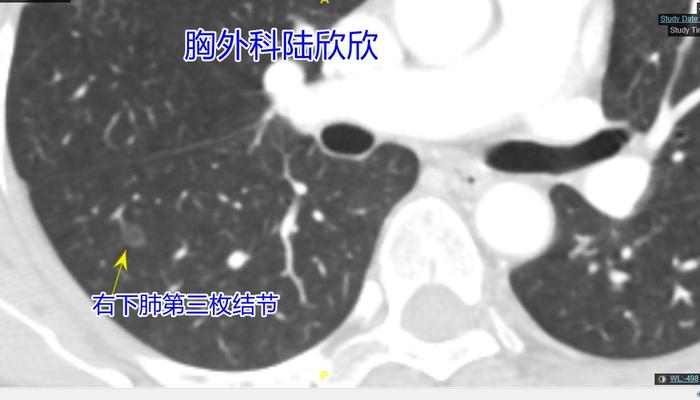

上图,右下肺背段的第三枚磨玻璃结节,6.4毫米,内部的黑缝是结节内部的支气管扩张,术前我考虑原位癌可能大,术后的病理是不典型腺瘤样增生